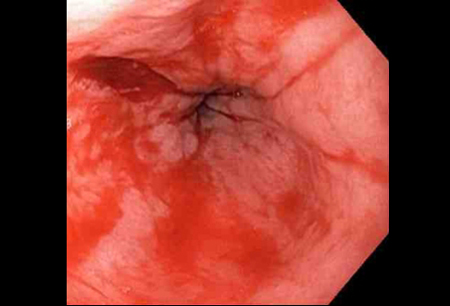

Actively bleeding tear appears as a red longitudinal defect with normal surrounding mucosa

From the collection of Juan Carlos Munoz, MD, University of Florida